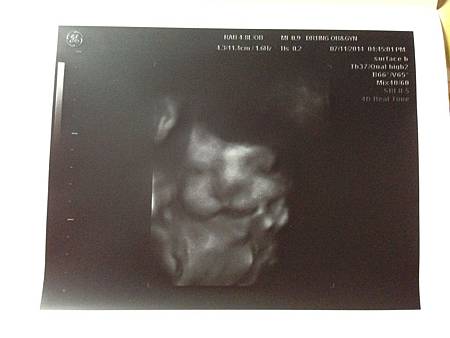

二妞報到

這一胎,過得很隨興~